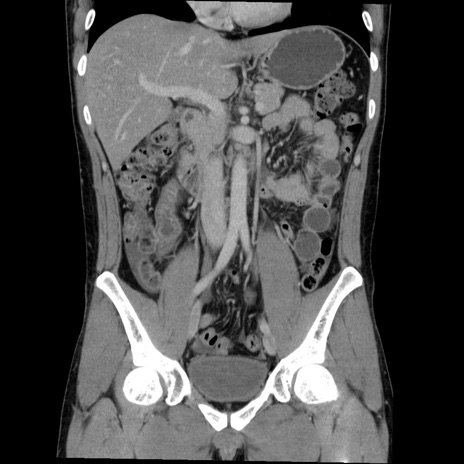

症例36(冠状断像)

【症例】20歳代 男性

【主訴】心窩部痛

【現病歴】今朝より上腹部痛あり。一旦軽快していたが再度出現したため救急要請。昨日夕に白身の魚を含む刺身を食べた。

【身体所見】BP 136/89mmHg、HR 74/min、BT 37.0℃、腹部:膨満、軟、心窩部に圧痛あり。反跳痛なし、筋性防御なし、腸雑音やや亢進あり。

【データ】WBC 17700、CRP 0.48